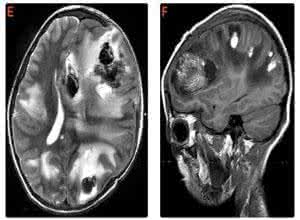

急性播散性脑脊髓炎是由于病毒感染或疫苗接种(如狂犬病疫苗或疫苗)引起的身体产生中枢神经系统的基本蛋白特异性序列的细胞免疫应答,导致血管周围神经的免疫反应,导致大脑和脊髓弥漫性炎症。

(3)一般认为急性播散性脑脊髓炎是一种免疫介导的中枢神经系统脱髓鞘性疾病。

急性播散性脑脊髓炎由什么引起的?它有哪些症状呢?急性播散性脑脊髓炎,是因病毒感染或疫苗接种(如狂犬病疫苗或牛痘)所致机体产生针对中枢神经系统碱性蛋白特异性序列的细胞免疫应答,导致血管周围神经免疫性应答,并引起脑和脊髓弥散性炎症。

(2)脑炎型首发症状为头痛、发热及意识模糊,严重者迅速昏迷和去脑强直发作,可有痫性发作,脑膜受累出现头痛、呕吐和脑膜刺激征等。脊髓炎型常见部分或完全性弛缓性截瘫或四肢瘫、传导束型或下肢感觉障碍、病理征和尿潴留等。可见视神经、大脑半球、脑干或小脑受累的神经体征。发病时背部中线疼痛可为突出症状。